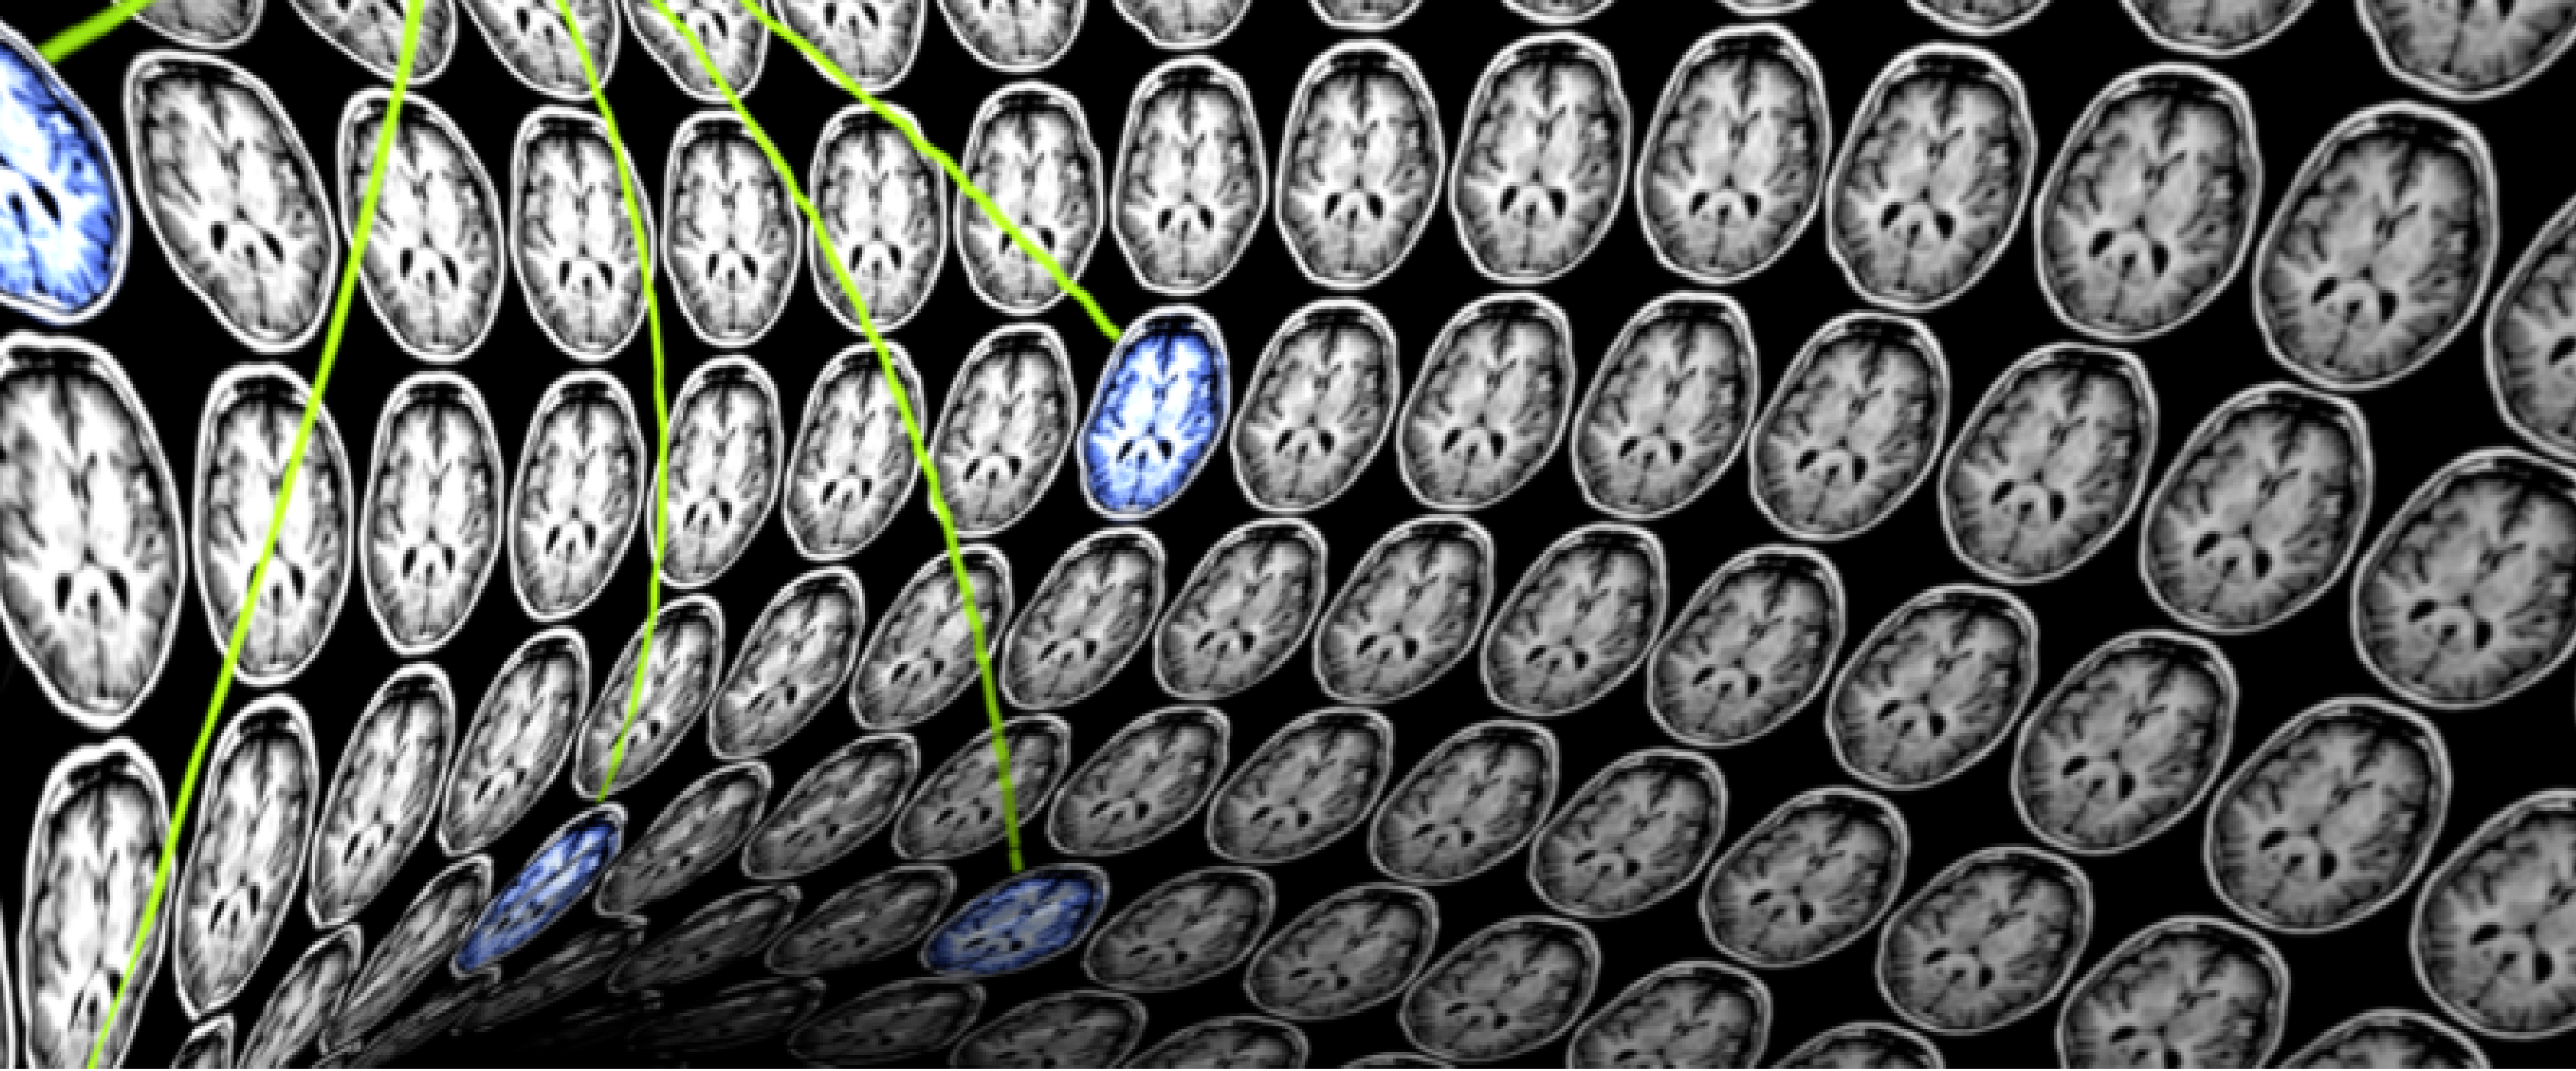

Nilearn Dev Days: science and software

19 - 22 mai 2020 // URL : TBA

Rejoignez en ligne la communauté de développement de Nilearn et déterminez la suite ! Deux jours d'exposés et deux jours de code sprint pour développer une communauté plus forte pour les statistiques sur les images du cerveau en Python.

En savoir plus

ICRA 2020 | Brain-PIL Workshop

31 mai 2020 // URL : TBA

Ce workshop vise à mettre en avant les défis actuels de la robotique et des systèmes autonomes qui peuvent être résolus en utilisant des approches inspirées du cerveau, et à partager les découvertes utiles des neurosciences qui peuvent révolutionner l'IA et la robotique.